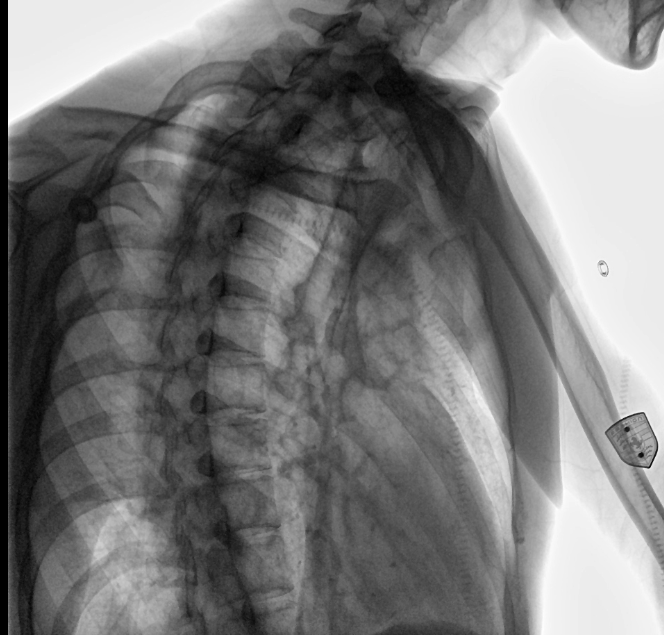

位于衡水市中醫(yī)醫(yī)院的動態(tài)平板數(shù)字化X射線系統(tǒng)DTP571具備高速高清點片功能。這是一款對放射科十分友好的產(chǎn)品。因為它把高速和高清點片結(jié)合,既能方便影像技師有效地抓拍需要的病灶的影像,又能給予影像醫(yī)生清晰的影像進(jìn)行診斷。

衡水市中醫(yī)醫(yī)院的放射科主任醫(yī)師于金厚主任為患者進(jìn)行檢查